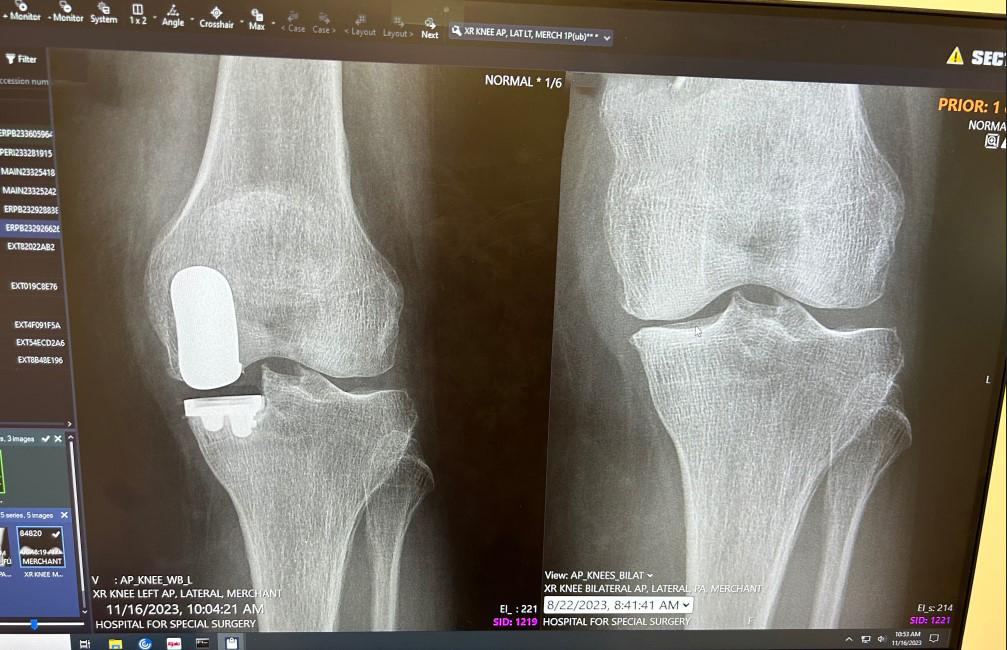

Robotic Knee Replacement Surgery

I started to exhibit pain in what I referred to as my “good knee” late in 2019. I had ACL surgery in my other knee almost 20 years ago due to a skiing injury. I started with my orthopedic group who performed that surgery and tried gel shots which worked for a short period of time. I recall what the surgery and recovery was like 20 years ago and was not looking forward to having my knee repaired. Due to a family member who had knee replacement surgery from Dr. David Mayman, he suggested I schedule a consultation. The entire process from the first visit to the visit after surgery and all in between was such a wonderful experience. Like most traveling to HSS from outside of NYC, they make this entire process streamlined and efficient. Dr. David Mayman spent the time to explain what and why he recommended partial knee replacement and what to expect with recovery and after. After that initial consultation my mind was made up to have surgery and I had no doubts. Once I started the process the online information shared, including informative videos narrated by Dr. Mayman, answered additional questions I had. After my own research, I knew I wanted robotic surgery and Dr. Mayman was the perfect choice to perform. It was amazing how fast I was able to get back to my normal life. The first couple of weeks, to be expected, brought back memories from my other knee surgery, but that’s when it differed. Each week after the pain was less and my range of motion increased, like I shared with others what now took weeks with my other surgery took months. At 5-6 weeks out I was back to my normal activities with some exceptions that I know I will be back to in the months ahead. It’s refreshing to not feel pain like I have been for the last year plus. I also opted for HSS Rehabilitation and Performance Virtual Care, which I couldn’t have been happier with. Best decision I made and happy to be back hiking, biking and all other activities with my family.